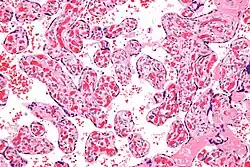

Micrograph of a chorangiosis. H&E stain. | |

Chorangiosis is a placental pathology characterized by an abundance of blood vessels within the chorionic villi.

It is diagnosed by a microscopic examination of the placenta.

Commonly used criteria from Altshuler[2][3] are: "a minimum of 10 villi, each with 10 or more vascular channels, in 10 or more areas of 3 or more random, non-infarcted placental areas when using a ×10 ocular." The Altshuler criteria are not theoretically rigorous, as they do not define the area. Normal villi have up to five vascular channels.[3]